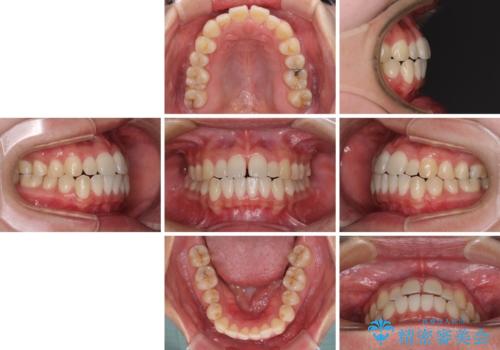

すきっ歯とオープンバイトをインビザラインで改善

- インビザライン

- 1年2ヶ月

- 前歯の上下スペースと前歯の隙間を気にして来院された患者様です。

インビザラインにより上下の前歯の隙間を閉じていくこととしました。

上下の隙間に舌が入り込むことが、すきっ歯やオープンバイトの原因であったため、舌の筋肉のトレーニングも並行して行い、後戻りの抑制を図りました。